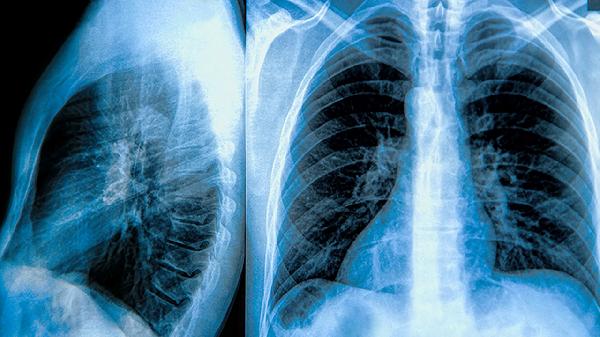

肺大泡晚期可通过胸腔闭式引流术、肺减容手术等方式治疗。肺大泡晚期通常由长期吸烟、慢性阻塞性肺疾病、肺部感染、遗传性α-1抗胰蛋白酶缺乏症、外伤性肺损伤等原因引起。

肺减容手术通过切除病变肺组织改善通气功能,适用于多发巨大肺大泡患者。手术需在全麻下进行,可采用胸腔镜微创技术。肺大泡进展可能与长期烟草暴露、慢性炎症刺激等因素有关,通常表现为活动后气促、咳嗽等症状。术后需配合呼吸康复训练,可遵医嘱使用氨溴索口服溶液、布地奈德福莫特罗粉吸入剂等药物缓解症状。